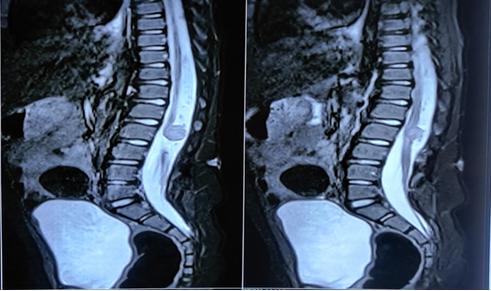

脊柱MRI显示硬膜内结节状病变(图2)在L2水平脊髓栓系的椎管后部,脊髓纵裂的特征(图3)和L4-5水平的背侧真皮窦,有脊髓栓系。CT扫描(图4)显示在L2、L3、L4、L5的后弓中的缺陷,以及在椎管、椎骨中的所有骶骨溶胶,在右侧L4/5小关节中注意到的部分融合,以及在椎管和L4/5水平的皮肤之间注意到的细的线性纤维化样束,可能是真皮窦。对颅脊髓轴进行筛查以排除脑积水和Arnold-Chiari畸形。根据临床和放射学表现,患者被安排手术。手术通过背部腰部区域的中线皮肤切口进行。暴露后,被证实为I型脊髓分裂畸形(SCM),硬膜外骨刺位于D12-L2椎骨水平。每个半索都有自己的硬膜囊和独立的脂肪脊髓脊膜膨出。使用高速钻在硬膜外显微镜下切除骨刺。硬脑膜以倒置的Y形方式打开。通过使用细致的显微神经外科解剖,对白线(脂肪瘤组织和脐带组织之间的界面)进行脂肪瘤组织的切除和脐带的解开。患者接受了脊髓松解术,同时切除了髓外硬膜内皮样肿块和脂肪瘤(图5和6)。术中模拟对肛周括约肌和下肢肌肉没有产生显著的反应。该患者接受了术中体感和运动诱发电位神经监测,未发现诱发电位间歇性降低。肿块的病理显示皮样囊性病变。

图2、脊柱T2 MRI显示约1.6×1.4×1.1cm大小的界限清楚的结节状病变,位于脊髓后L2椎体水平,提示硬膜内髓外皮样瘤,病变前部脊髓栓系